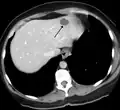

Liver

Infantile haemangiomas in the liver are found in 16% of all liver haemangiomas. Its sizes are usually less than 1 to 2 cm in diameter. It may show a "flash-filling" phenomenon in which there is the fast enhancement of the contrast material in the lesion instead of slow, centripetal, nodular filling of the lesions in usual hemangiomas. On CT and MRI, it shows rapid filling during arterial phase, with contrast retention in venous and delayed phases.[38]